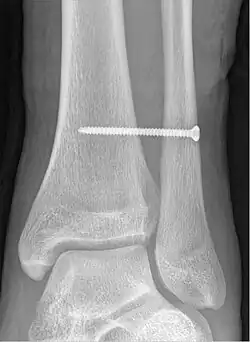

Syndesmotic screw

A syndesmotic screw is a metal screw designed to replace the syndesmosis of the human body, usually temporarily. If the syndosmosis is torn apart as result of bone fracture, surgeons will sometimes fix the relevant bones together with a syndesmotic screw, temporarily replacing the normal articulation.

A syndesmotic screw designed to replace the inferior tibiofibular articulation that fix the tibia and fibula together at the lower joint, is 5–6 cm long and made of a stainless, solid metal.